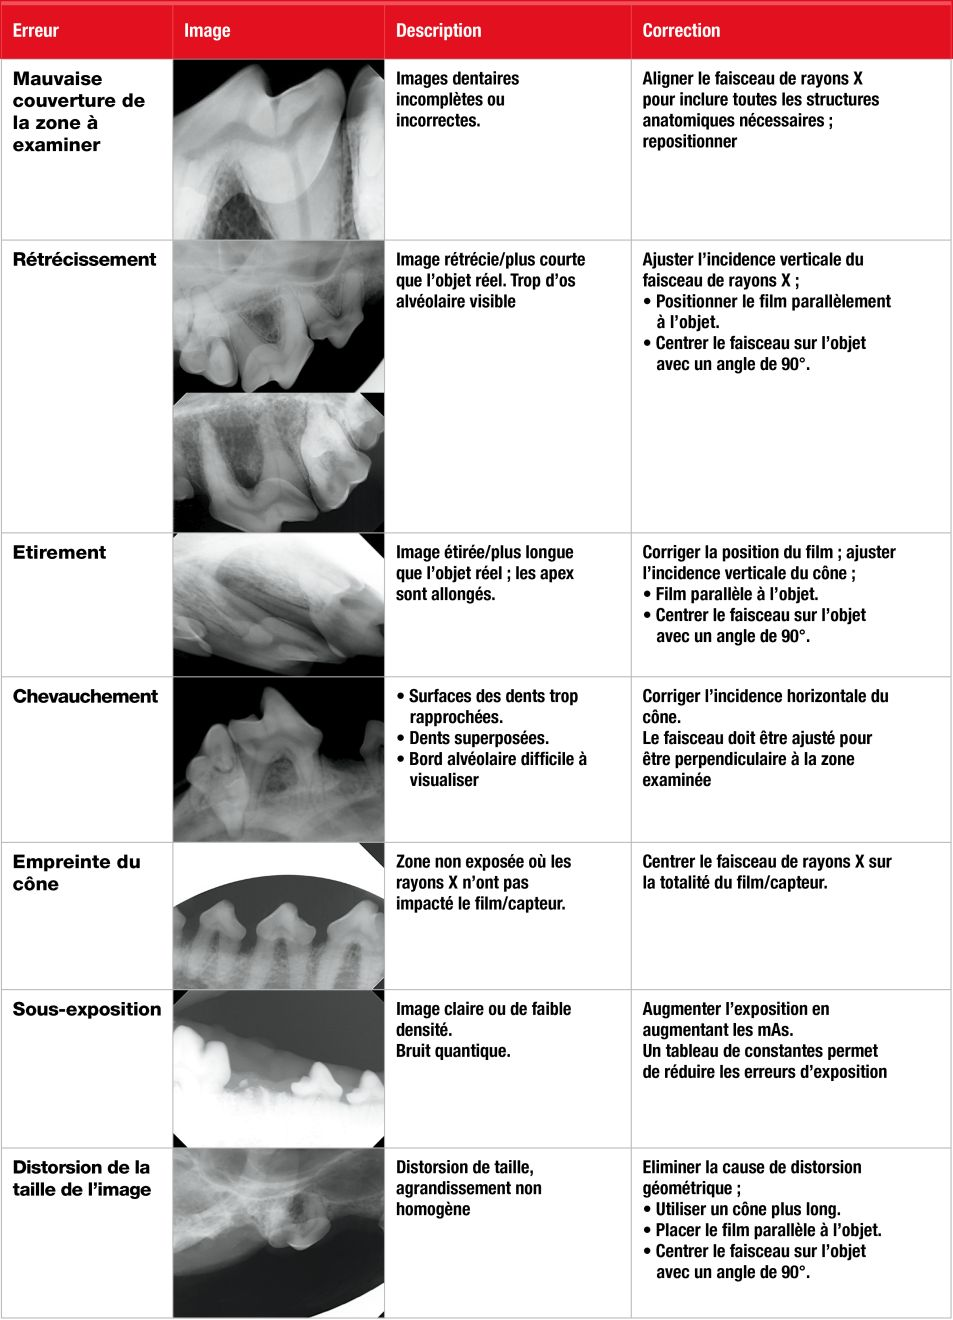

Des erreurs techniques peuvent survenir à n’importe quelle étape. Elles peuvent être liées au positionnement du film, à celui de l’animal, à l’angle d’incidence du faisceau de rayons X, à l’exposition, au traitement du film, à son stockage ou à plusieurs de ces éléments en même temps. Le Tableau 1 liste les problèmes les plus fréquemment rencontrés et leurs solutions.

Tableau 1. Erreurs courantes en radiographie dentaire.